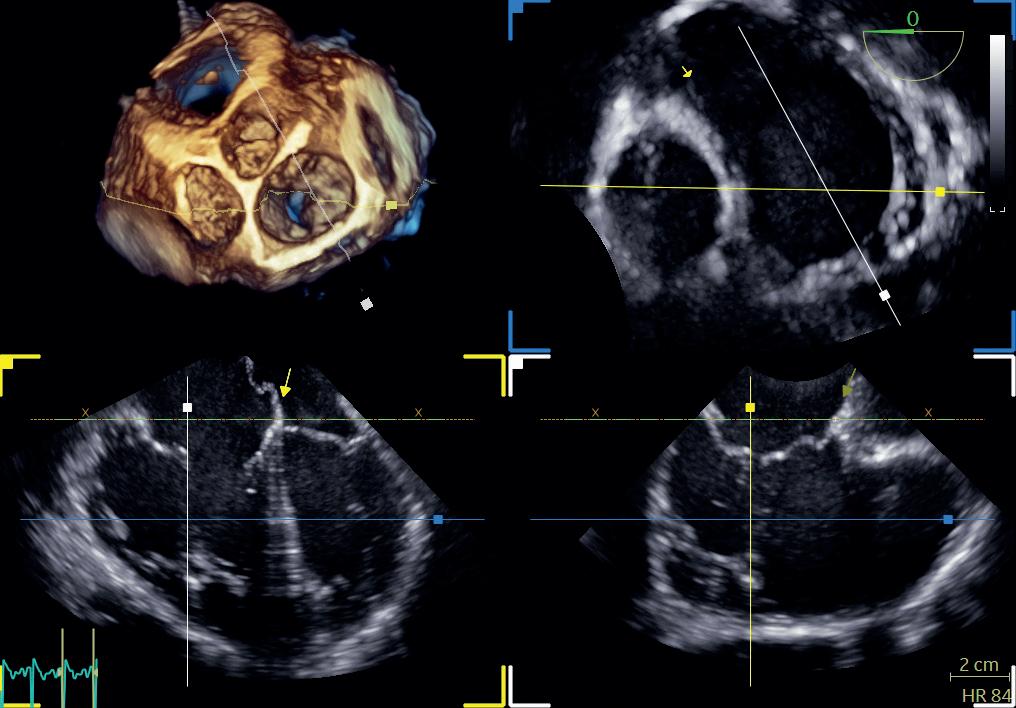

3D-ekkokardiografi

Utviklingen innen ekkokardiografi med bedre datakraft, økt prosessorkapasitet, analysemuligheter og transdusere med flere piezoelektriske elementer arrangert i en matrise som kan lage pyramidale datasett, har gjort det mulig å gå fra 2D-ekkokardiografi til 3D-ekkokardiografi. Da vil hjertet i tre plan kunne fremstilles i sanntid. 3D-opptak kan gjøres over ett eller flere hjerteslag, og selv om tids- og bildeoppløsningen taper seg noe sammenlignet med 2D-ekkokardiografi, vil det romlige forholdet mellom strukturene i hjertet komme bedre frem. Vi slipper dermed å ta forbehold om hjertets geometri, slik vi må gjøre når vi ser hjertet i kun to plan. Målingene blir mer nøyaktige og reproduserbare, og hjerteklaffene kan visualiseres på en ny måte (figur 1.7).

Teknikken er i økende grad i bruk og er i visse situasjoner og ved enkelte sykdomstilstander svært nyttig. Den kliniske nytten viser seg for eksempel ved måling av hjertekamrenes volum, masse og EF, ved vurdering av klaffenes anatomi og visse klaffefeil, ved medfødte hjertefeil, intrakardiale lesjoner og i forbindelse med operative eller perkutane inngrep.

En sentral utfordring med 3D-ekkokardiografi er kompromissene mellom tidsoppløsning og lateraloppløsning. Dette kan delvis løses ved å «stifte sammen» delvolumer fra flere hjertesykluser, men ved uregelmessige hjerterytmer eller dersom pasienten beveger seg mye under opptakene, vil datasettene «stiftes» ujevnt sammen og det oppstår artefakter. Undersøkelsen krever også en del tid og kompetanse, og det kan være mer utfordrende å få gode bilder fordi 3D-transdusere er større enn 2D-transdusere og innsynet interkostalt vanskeliggjøres. Det kan være krevende å orientere seg i 3D-opptak når man ser på mindre avsnitt av hjertet, så det er derfor nyttig å lære seg de standardiserte bildeplanene for 3D.

Figur 1.7: Transøsofageal ekkokardiografi (TØE) med 3D-opptak som fremstiller basis av hjertet med alle fire hjerteklaffer øverst til venstre, og multiplan rekonstruksjon øverst til høyre og nederst